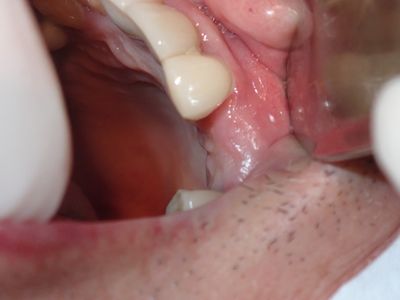

relatively straightforward implant placement. Densah drills used to avoid perforating buccal bone.